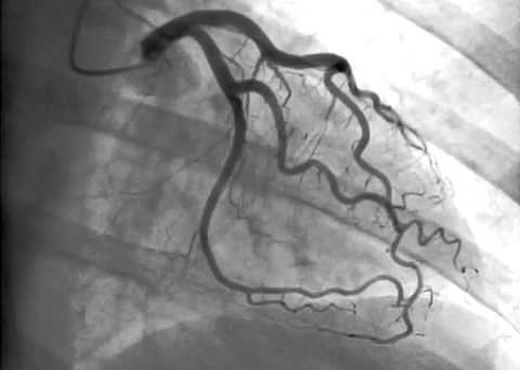

EN EL CORAZÓN

A través de estos procedimientos podemos tratar enfermedades de las arterias del corazón, que producen síntomas como angina (dolor en el pecho), disnea o falta de aire intensa y sensación de desmayo.

Estos procedimientos nos permiten mejorar el flujo sanguíneo en arterias coronarias estrechas o bloqueadas.